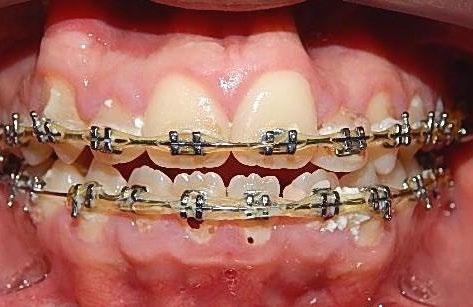

El tratamiento se realizó en las siguientes fases: la fase prequirúrgica incluyó la alineación, nivelación y la

extracción de los segundos premolares superiores e inferiores, con cierre de espacios. En la fase quirúrgica, se realizó una mentoplastia de avance e implantes en la zona malar. La fase postquirúrgica consistió en el detallado-retención. La aparatología utilizada fueron brackets de prescripción Roth .022 × .028; se colocaron bandas en los primeros molares superiores e inferiores, con tubos punteables en los O.D. 16, 26, 36 y 46, y tubos bondeables en el O.D. 27, además de un arco transpalatino y un arco lingual.

El tratamiento se realizó en las siguientes fases: la fase prequirúrgica incluyó la alineación, nivelación y la extracción de los segundos premolares superiores e inferiores, con cierre de espacios.

El tratamiento concluyó en 2 años y 6 meses, logrando el perfil facial deseado, con clase I esquelética, clase I canina y molar bilaterales, corrección del apiñamiento maxilar y mandibular, líneas medias coincidentes, overjet y overbite adecuados, así como la realización de la genioplastia e implantes en la zona malar. En los

En los estudios finales en las fotografías intraorales (Figura 9) se ve la línea media coincidente, el overjet y el overbite. La alineación y forma de las arcadas superior e inferior, con el

Figura 9. Lateral derecha frente, izquierda final.

Figura 10. Oclusal superior inferior final.

retenedor fijo de premolar a premolar (Figura 10).